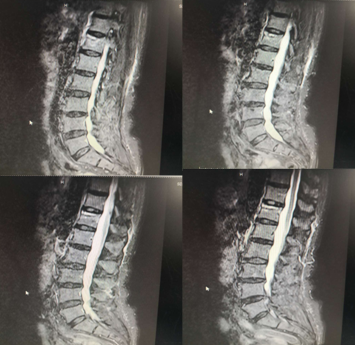

术前MRI

术后2周MRI

术前

术后2周